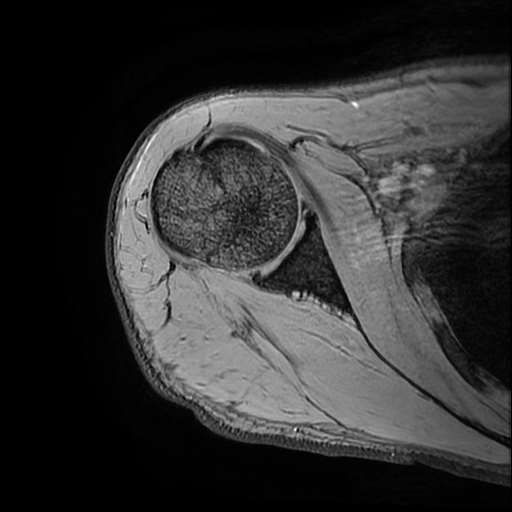

오른쪽 어깨 와순파열 및 점액낭염이 보인다고 하는데 상태를 알고 싶습니다

MRI 사진상 와순파열 점액낭염 등이 있다고 하는데..심한 상태인가요?

MRI상 와순파열, 회전근개 부분파열 등이 있으며 일부 염증소견이 있습니다.

주사, 약물, 물리치료 등에 통증이 호전을 보인다면 경과관찰을 해볼 수도 있겠지만 어깨관절의 불안정성 및 통증이 심하신 상태라면 관절경을 이용하여 수술적 치료를 받으시는 것을 추천드립니다.